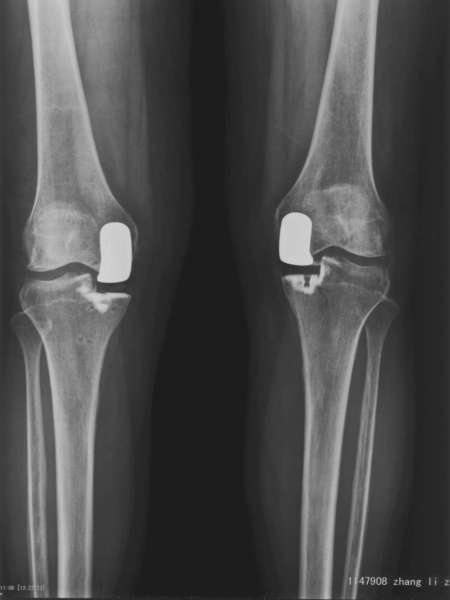

膝关节分为三个间室,分别为内侧间室、外侧间室、髌股间室。膝退行性关节炎可以影响其中任何一个间室,1/3的膝关节炎病人早期病变仅局限一个间室。目前治疗单间室关节炎手术方法有单髁关节置换 (unicompartmental knee arthroplasty ,UKA)、胫骨高位截骨(high tibial osteotomy, HTO)和全膝关节置换(total knee arthroplasty ,TKA)。胫骨高位截骨主要适用于年龄较轻、活动量大、体型肥胖的患者,并且该术式作为向全膝关节置换的过渡治疗术式,存在缓解症状不完全、疗效维持短的缺点,在年龄较大的人群中使用较少。而单髁关节置换术由于假体设计、病例选择、手术技术改进,越来越受到人们关注。我科自2003年起开展单髁关节置换术。现在的UKA手术效果令人鼓舞, Berge2005年报道Miller-Galante假体13年生存率为98%;。Cartier2007年报道161膝UKA10年生存率为94.5%;。我们科自2003年开始开展此项技术,早中期的效果良好。

UKA与TKA相比,手术失血少、恢复快、可以早期下地活动、住院时间短、术后功能好、住院费用低。我们的结果验证此点。另外,有学者发现UKA与TKA相比在提高本体感觉尤其在关节活动觉方面更优。这显然与保留了更多的自体组织是相关的。

UKA与TKA比较,早中期并发症发生率相似,在改善功能(术后关节活动度、疼痛缓解)方面相似,但损伤小、恢复快、费用低,是治疗单间室关节炎值得考虑的手术选择。